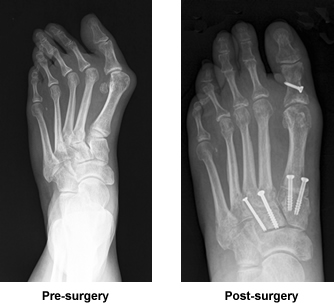

I was referred to Dr. Leavitt by a local podiatrist for surgery on my left foot for a bunion, hammer toe, three toes which were crossed, and the large toe which turned inward. This made me appear to walk side wards. The local podiatrist advised me if I was going to have it done, by all means I should have Dr. Leavitt do the surgery as "he was the best."

I finally underwent surgery on 5/6/11 at the New England Baptist Hospital. I was in surgery for five hours but fortunately was able to return home the same day. I followed Dr. Leavitt's instructions to the letter. I rented a "Roll-A-Bout" which enabled me to get around in my home while keeping my foot off the floor which gave me independence as I was not a candidate for crutches. I had to remain non weight bearing for two to three months.

After 12 weeks I was able to return to work with my foot still swollen at times but with perfectly aligned toes. I would have to agree with my local podiatrist that "Dr. Leavitt is truly the best." I remember seeing a needlepoint sign in his office that said "Take good care of my work." I did. I followed his instructions and had minimal discomfort.